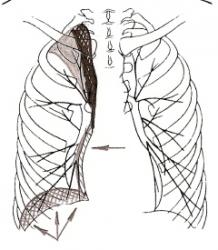

Ниже приведены схемы спадения долей и сегментов (по Anacker H., 1963) – иллюстрации 11, 12, 13.

Для своевременной диагностики, как долевых, так и сегментарных ателектазов необходимо уделять внимание следующему:

- положение и наличие деформации междолевых и межсегментарных щелей;

- степень спадения отдельных структурных единиц лёгкого;

- закономерности их перемещения при спадении;

- состояние окружающих тканей лёгкого;

- возможности перемещения диафрагмы, средостения и здорового лёгкого – иллюстрация 14.